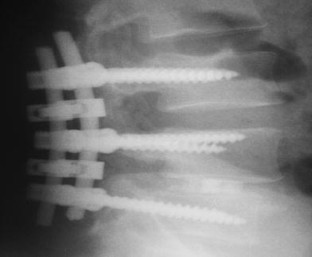

We report a case of L4–L5 traumatic anterolisthesis. The patient was treated surgically 4 months after the injury. His radiological and operative findings showed L4 inferior facet tip fracture, L4–L5 anterior displacement and left L4–L5 foraminal disc protrusion. Decompression, reduction with L3, L4, L5 pedicular screw fixation, L4–L5 disc excision and interbody cage insertion with autologous bone grafts were done. Flexion type injury was thought to be the probable mechanism.

Fig. 1